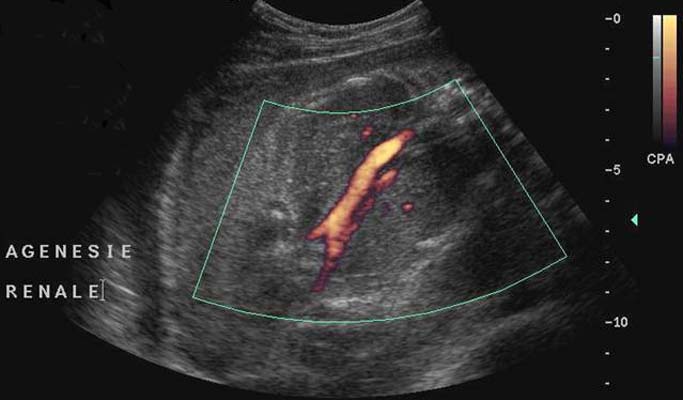

Thrombose veineuse